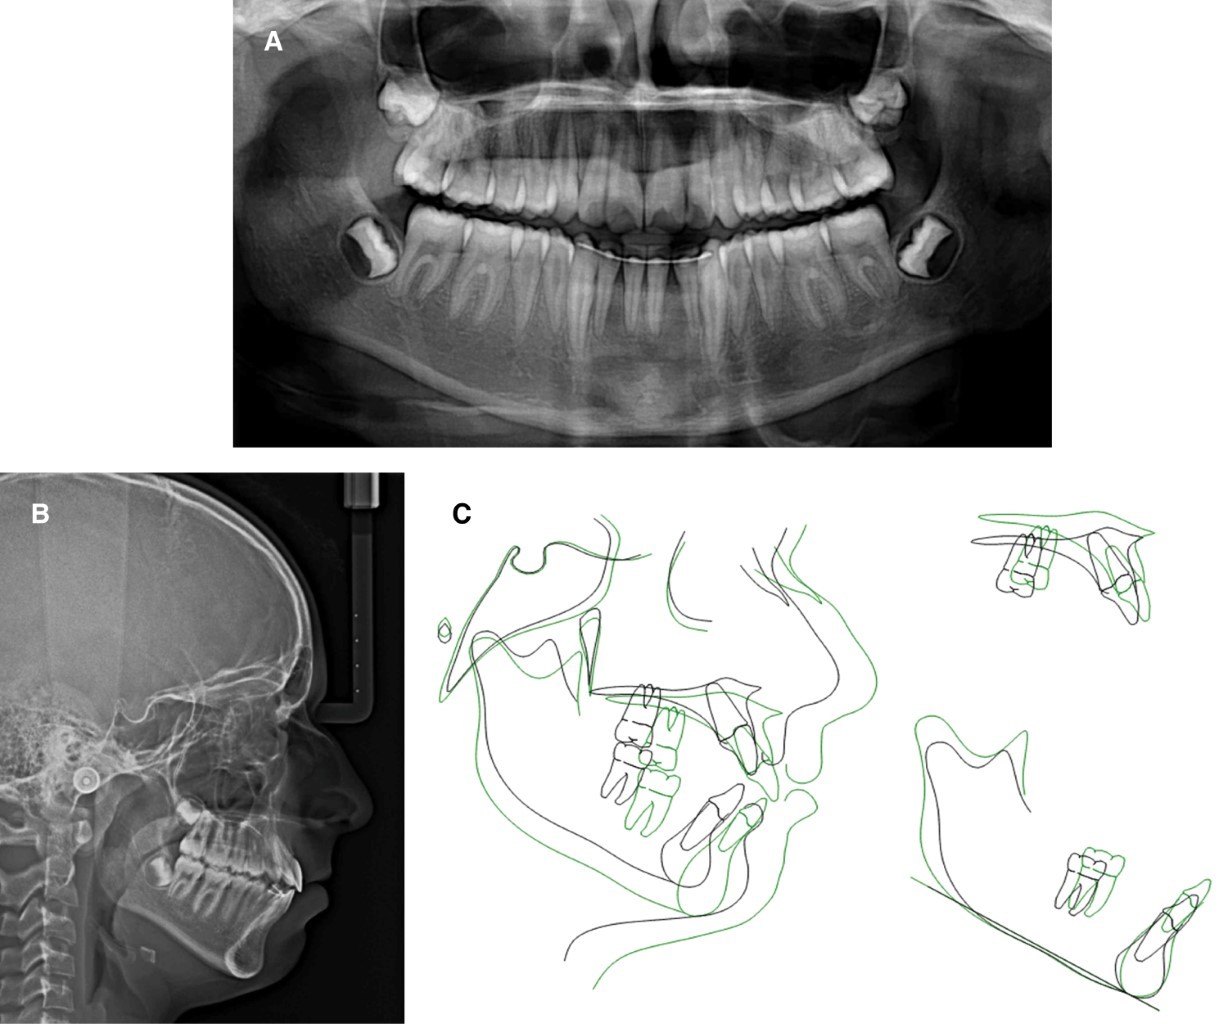

En la radiografía panorámica (Figura 3A) se observan dientes permanentes por erupcionar, cóndilos aparentemente sanos y vías aéreas ligeramente obstruidas.

Se diagnosticó como una clase II división 1 esqueletal con tendencia a clase III por hipoplasia del maxilar, compensando por una rotación mandibular en sentido de las manecillas del reloj, como se muestra en la Figura 3B y Tabla 1.

Figura 3